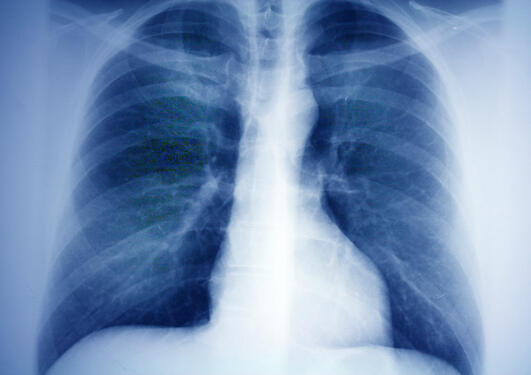

The data generated by the huge RHINESSA, ECRHS and RHINE surveys are clearly showing that not only mothers’ health, and in utero exposures, but also that fathers’ health is critical for offspring health. In addition, it seems that there is a critical susceptibility window, or window of vulnerability, in early adolescence (less than 15 years old) in boys that is worthy of attention for efficient, effective public health initiatives that will improve child health in the next generations. During this pre / early adolescent period, germ cells undergo extensive epigenetic reprogramming as they develop into mature reproductive cells.

In particular, researchers have identified two factors that correlate strongly with offspring health in the first AND second generations: whether the boy is overweight and whether the boy uses nicotine products (cigarettes, e-cigarettes, chew tobacco).